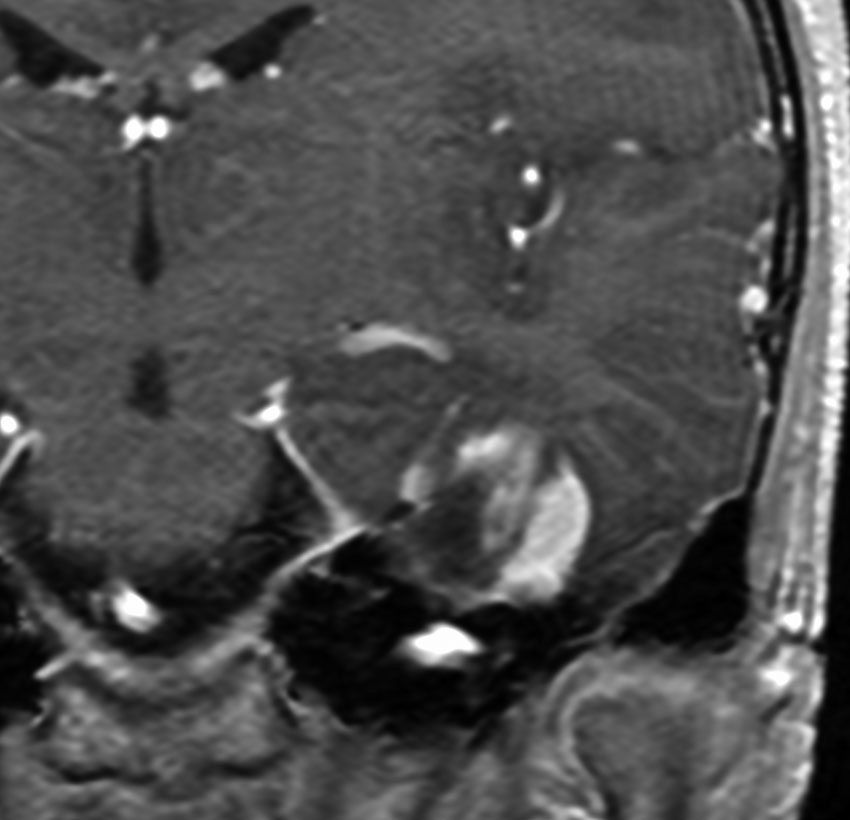

神経線維腫症1型に合併した退形成を示す anaplastic PXA

もともと停止性水頭症があり経過観察を受けていたNF-1の患者さんに発生したものです。嘔気と左片麻痺で発症しました。 開頭手術で亜全摘出(ほぼ全摘)しました。

術後に小さな腫瘍が残っていた(左の画像)ので54Gy/27frの放射線治療をしましたが,無効でした。結局,再開頭手術で残存腫瘍を摘出しました。3年後に同じ部位で再発(中央の画像)したので,また開頭手術で摘出しました。そのまた3年後に同じ部位で再発しました(右側の画像)。この様に,摘出しきれなければ治らないし,摘出できれば治る可能性の高い腫瘍です。腫瘍床での再発は多いものの,転移とか脳深部への浸潤性増殖は少ないといえる腫瘍です。放射線治療が効きにくいということを併せて,atypical meningioma WHO grade 2と似た性格を有しています。